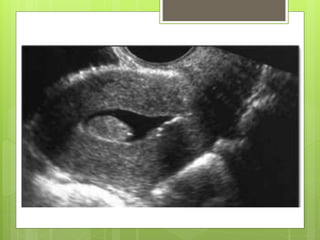

SONOHISTEROGRAFIA

 Técnica mediante la cual dentro

del , a través del cuello uterino, y se usa

la para proyectar imágenes de la

cavidad uterina.

 El líquido revela con más detalle el

 Generalmente dura unos 15 minutos.

 Técnica de ultrasonidos especial, mínimamente

invasiva, que proporciona imágenes del interior

del útero de la mujer.

 La histerosonografía puede evitar intervenciones

quirúrgicas innecesarias.

SONOHISTEROGRAFIA  Técnica mediantela cual dentro del , a través del cuello uterino, y se usa la para proyectar imágenes de la cavidad uterina.  El líquido revela con más detalle el  Generalmente dura unos 15 minutos.

 Técnica deultrasonidos especial, mínimamente invasiva, que proporciona imágenes del interior del útero de la mujer.  La histerosonografía puede evitar intervenciones quirúrgicas innecesarias.